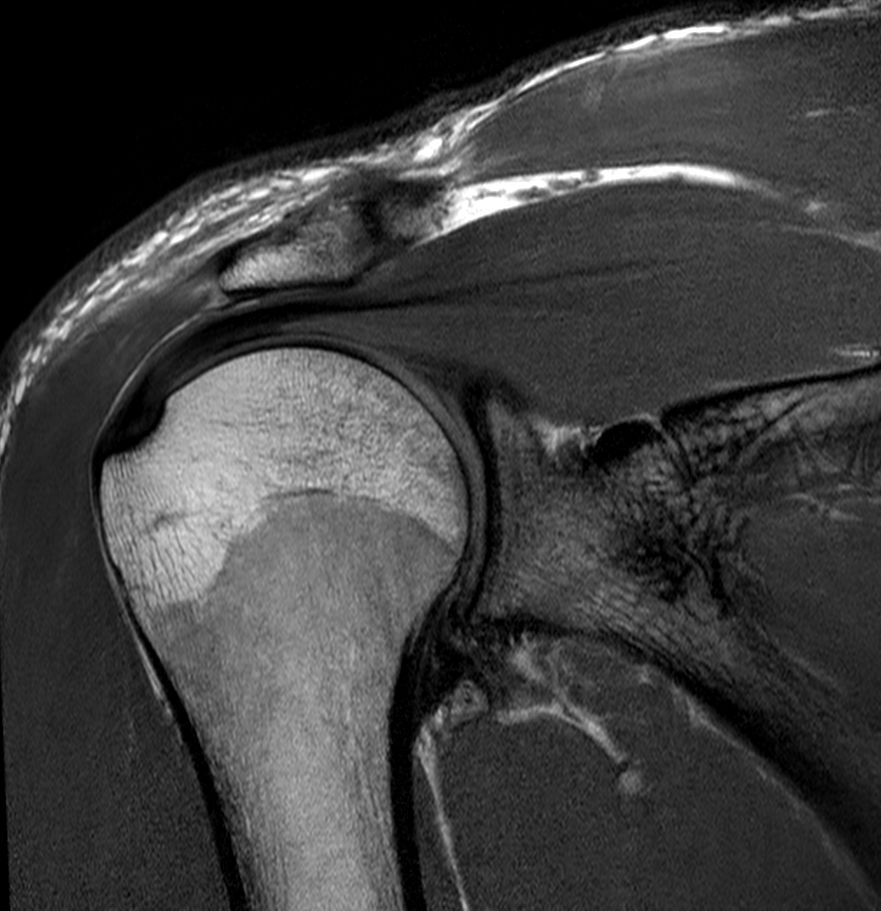

Coronal PDw TSE